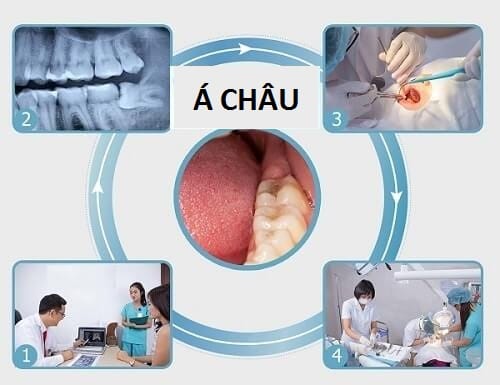

Nhổ răng là phương pháp mà bác sĩ chỉ định nhằm tạo khoảng trống giúp răng di chuyển về vị trí mong muốn. Phương pháp nhổ răng để niềng răng được áp dụng khi niềng răng ở tuổi trưởng thành bởi khi này xương hàm đã cứng chắc khó mà tạo khoảng trống để di chuyển các răng mọc lệch lạc.

Khá nhiều bệnh nhân được chỉ định nhổ răng trước khi niềng răng, có trường hợp cần nhổ đến 8 răng chứ không phải 4 răng như của Minh Vũ. Tuy nhiên, những ca nhổ răng trước đó đã cho thấy việc nhổ răng để niềng không hề ảnh hưởng đến sức khỏe hay sức ăn nhai của bạn.

Trước khi chỉ định nhổ răng để niềng, bác sĩ sẽ phải tính toán tỉ mỉ, chính xác lộ trình răng di chuyển để xem nhổ răng có bắt buộc hay không, đồng thời chỉ định cần nhổ bao nhiêu chiếc răng. Vì thế, bạn không cần quá lo nghĩ nhổ răng để niềng có ảnh hưởng gì không khi lựa chọn bác sĩ chỉnh nha giỏi, có kinh nghiệm lâu năm.

Lo lắng này cũng được loại bỏ khi bạn được ứng dụng công nghệ nhổ răng hiện đại, do các bác sĩ giỏi phụ trách. Bởi vậy, nha khoa Á Châu sẽ là địa chỉ để bạn có thể tin cậy với công nghệ nhổ răng không gây đau nhức nhờ kỹ thuật gây tê hiện đại, cùng đội ngũ hơn 50 chuyên gia nha khoa chuyên sâu về từng lĩnh vực, trong đó có cả về nhổ răng.

Thuốc tê mà nha khoa Á Châu sử dụng được nhập khẩu từ Pháp và đã qua kiểm định của Hiệp hội nha khoa Pháp ADF về độ an toàn, cũng như tác động mạnh hơn các loại thuốc thông thường, giúp xua tan những cơn đau nhức.

Bằng những dụng cụ nha khoa chuyên dụng, bác sĩ chỉ tác động đến phần cứng của răng để làm đứt các dây chằng nha chu và dễ dàng lấy răng ra vì thế hạn chế tối đa chảy máu, thu nhỏ độ rộng của vết thương.